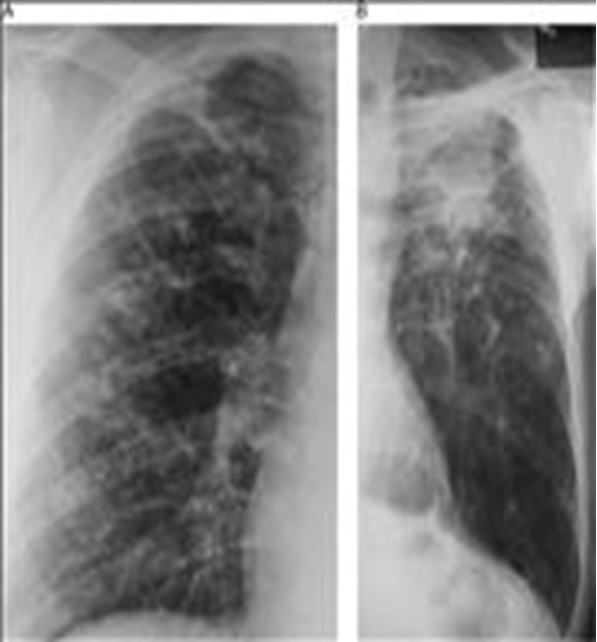

Заболевания легких: Симптомы пневмокониоза